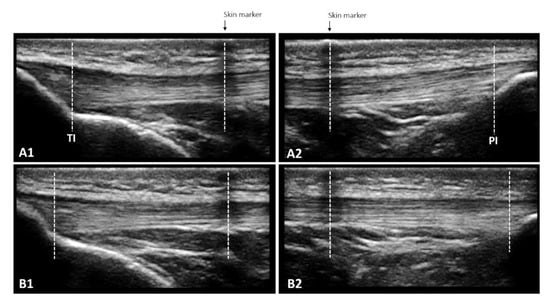

2.5.3. Muscle Architecture Assessment

2.5.4. TAC Stiffness

2.5.5. Patellar Tendon Properties

Morphological Properties

Mechanical Properties